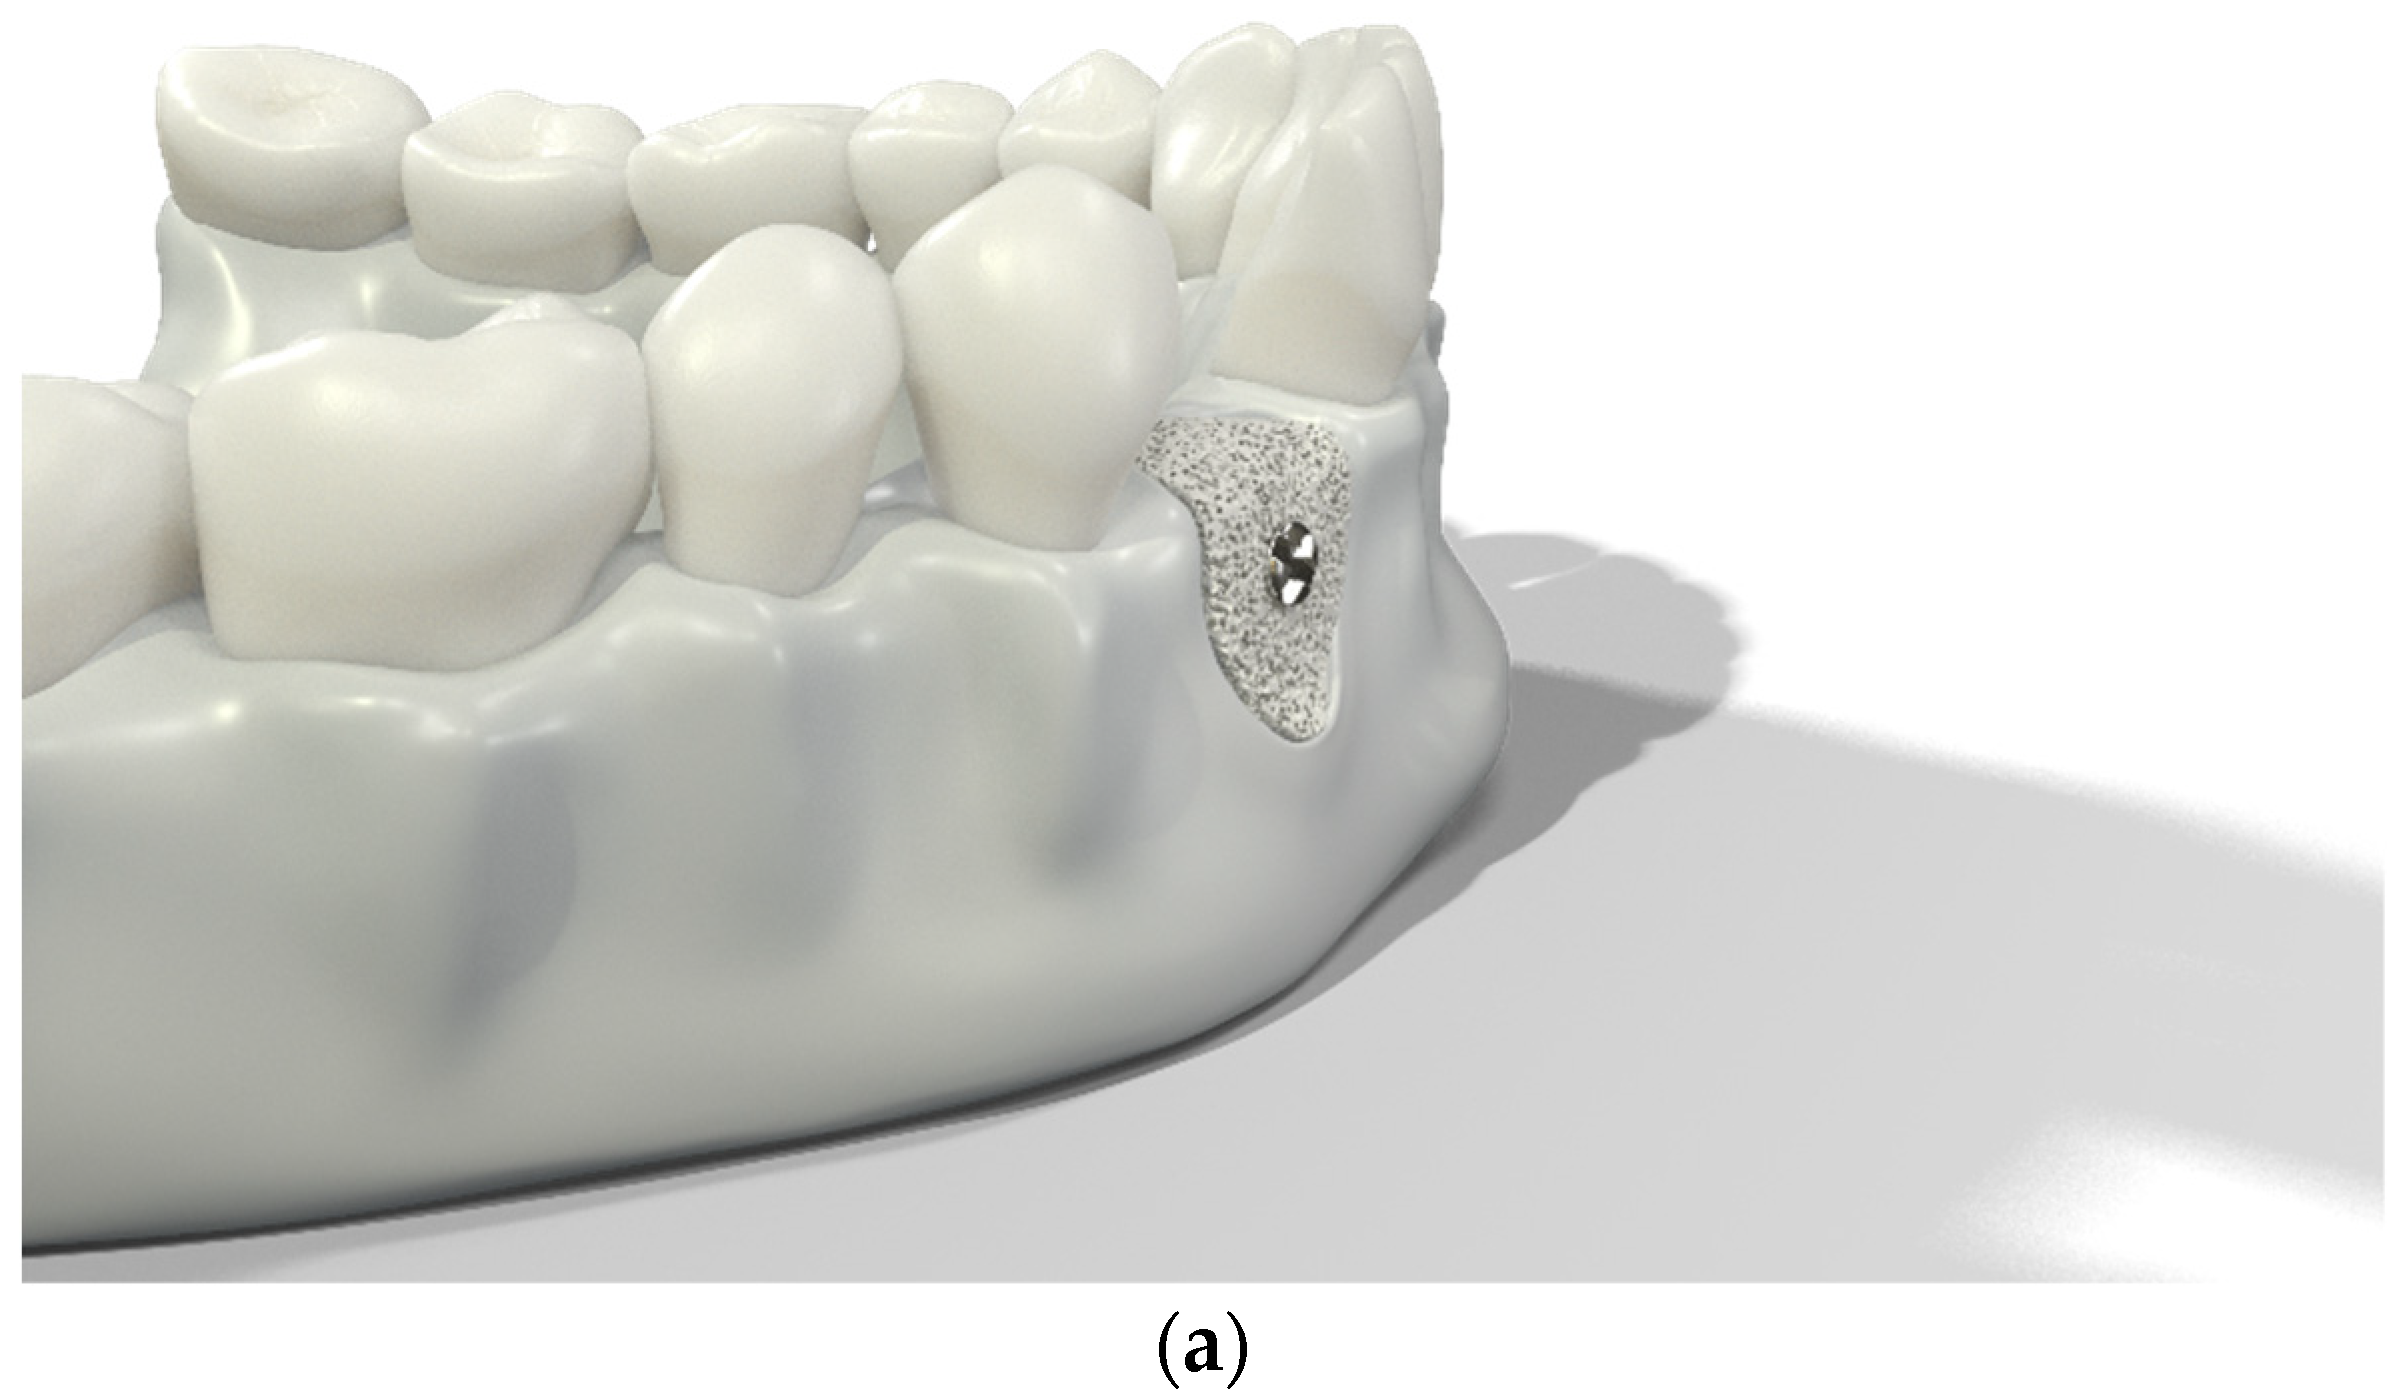

Over-contouring was defined as an over-augmentation of the alveolar process beyond the extent of the adjacent bone level (Figure 1). The reason for over-augmenting the alveolar process is often an anticipated shrinkage of the bone substitution material during the healing phase. Two patients were selected as examples to illustrate the term “over-contouring”. Patient 1 showed a Class III defect in the maxilla, and the alveolar ridge augmentation performed for correction was over-contoured (Figure 2). Patient 2 also showed a Class III defect in the maxilla, but the alveolar ridge augmentation performed for correction remained at the level of the surrounding bone (Figure 3).

Figure 1.

Graphical 3D models to demonstrate surgical over-contouring during augmentation of the alveolar process. (a) Lateral view of the mandible with a single-tooth gap on the position of the second right incisor; the bone defect was compensated without exceeding the extent of the adjacent bone level. (b) Lateral view of the mandible with a single-tooth gap on the position of the second right incisor; the bone defect was over-compensated by an over-augmentation of the alveolar process beyond the extent of the adjacent bone level. This is defined here as “over-contouring”. (c) Isometric view of the mandible with a single-tooth gap on the position of the second right incisor; the difference between appropriate augmentation (left half) and over-contouring (right half) is clearly visible. (d) Lateral view of the mandible with a single-tooth gap on the position of the second right incisor; the difference between appropriate augmentation (left half) and over-contouring (right half) is easily recognizable.